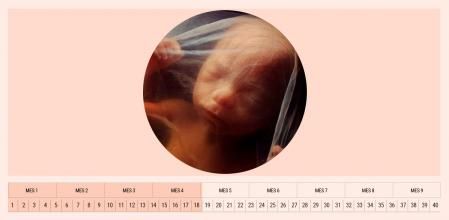

El embarazo sigue avanzando y, con él, se producen importantes cambios tanto en el desarrollo del feto como en el cuerpo de la madre. En la semana 18 el corazón del bebé avanza en su formación, mientras que muchas mamás ya notan sus movimientos dentro del vientre.

Algunas ya llevan percibiendo un burbujeo desde la semana 16, mientras que otras –sobre todo las primerizas– quizá tengan que esperar hasta la número 20 para apreciarlo. En cuanto a las dimensiones del bebé, en la semana 18 de embarazo mide entre 13 y 14 centímetros y pesa ya 150 gramos. Para compararlo con un vegetal, es similar a un boniato o una papaya pequeña.

Cambios en el bebé en la semana 18 de embarazo

Uno de los avances más significativos en el desarrollo del feto tiene que ver con su corazón. En este momento se divide en cuatro cámaras –dos aurículas y dos ventrículos– y cuatro válvulas –aórtica, tricúspide, mitral y pulmonar–. Ahora, la sangre pasa de la aurícula derecha a la izquierda por un agujero llamado foramen oval. De este modo, la sangre no circula por los pulmones. Sin embargo, este orificio se cierra al nacer el pequeño.

Progresa a pasos agigantados su sistema digestivo. Traga líquido amniótico que pasará a su estómago y luego a los intestinos, procesando células muertas y secreciones. La vesícula biliar también empieza a funcionar.

Asimismo, el bebé tiene ya huellas dactilares en los dedos de las manos, sus orejas sobresalen a los laterales del cráneo y el cartílago de su cuerpo va transformándose lentamente en hueso. Otro dato relevante es que ya empieza a escuchar sonidos.